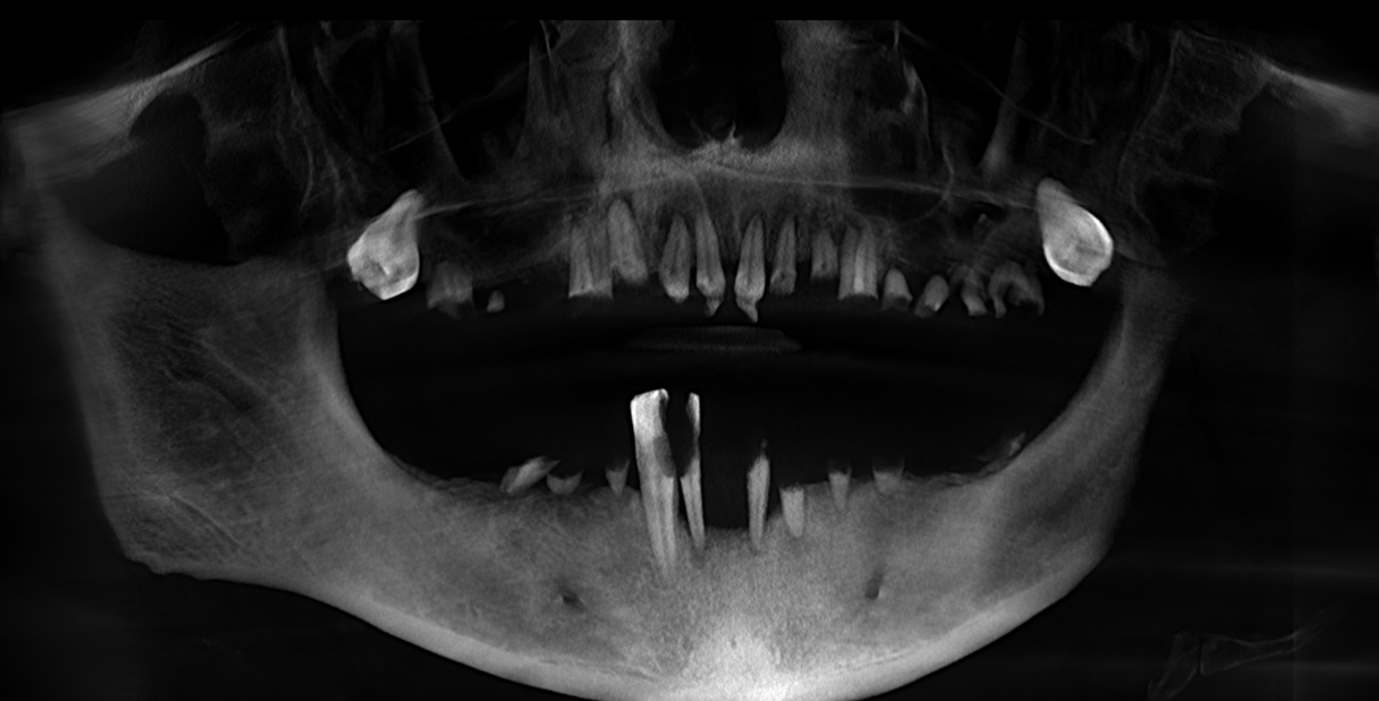

• OPG x-ray

• CBCT scan

These records allowed us to carefully evaluate bone levels, gum health, and ideal implant positioning.

Although the patient showed moderate bone loss in certain areas and signs of previous chronic infections, his overall bone quality remained suitable for implant treatment. Importantly, there was no active infection at the time of surgery.

• placement of 5 implants in the upper jaw

• placement of 6 implants in the lower jaw

The surgery took approximately four hours. During the procedure, intraoperative x-rays were taken to confirm precise implant placement.

Dr Rashi Gupta explains that this patient was a strong candidate for implants due to good general health and sufficient bone support.

She emphasises that detailed CBCT planning is one of the most critical aspects of treatment, as it ensures precision, reduces risk, and supports long-term success.